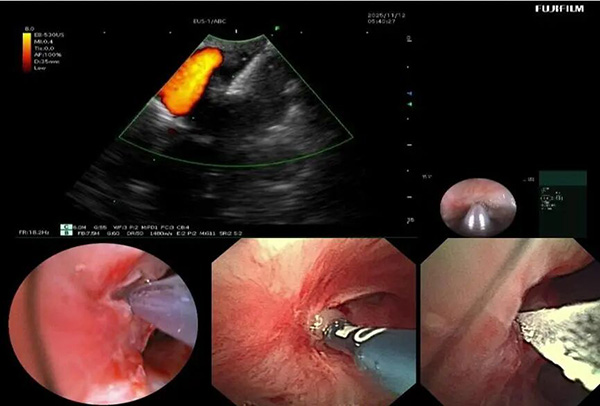

入院后,呼吸与危重症医学科介入团队对患者病情进行全面评估。完善胸部增强CT提示:右肺上叶大片状实变并坏死,支气管完全闭塞。由于前期单纯口服抗真菌药物效果不佳,因此联合气管镜下介入治疗势在必行。经过认真评判,团队制定了详细的气管镜下介入诊疗计划。治疗过程包括:超声支气管镜引导下精准穿刺,高频电刀微创开窗建立引流通道;钳夹清除远端大量坏死组织;局部灌注抗真菌药物以提高病灶药物浓度;结合球囊扩张与超细冷冻冻融治疗,扩大引流窗口;并多次行镜下冲洗,彻底清除分泌物与坏死物。

▲支气管镜下多种内镜器械联合使用

▲呼吸介入团队进行镜下治疗

经过系统治疗,患者低热症状消失,精神状态逐步好转。术后气管镜复查显示右上叶前段闭塞支气管已重新开放,坏死物基本清除;胸部CT显示原新发病灶消失,前段病灶引流通畅,炎症吸收良好,成功保留了右肺功能。